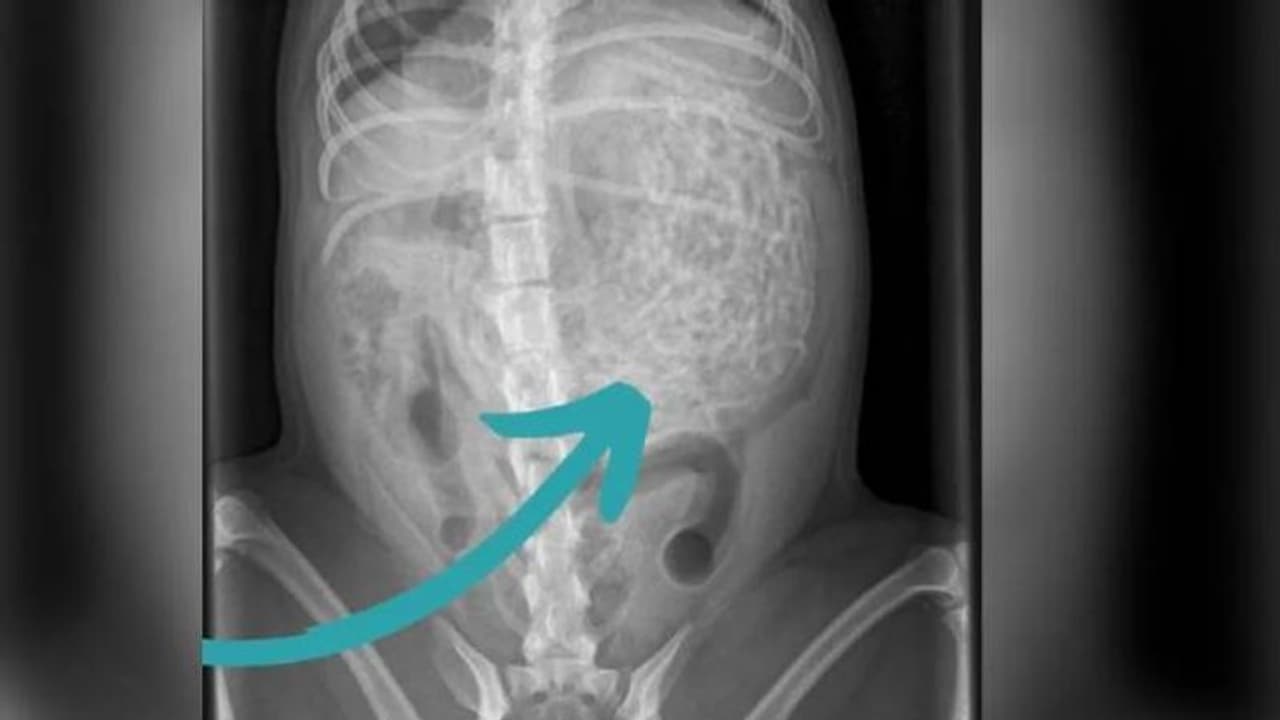

ഹാമിനെ പരിശോധിച്ച ന്യൂട്ടൺ ക്ലാർക്ക് വെറ്ററിനറി സർജറിയിലെ സംഘം പറഞ്ഞത് അവളുടെ വയറ്റിൽ അസാധാരണമായ എന്തോ ഒന്നുണ്ട് എന്നാണ്. അവസാനമാണ് ഈ അസാധാരണമായ സംഗതി 200 ഗ്രാം വരുന്ന ഹെയർബാൻഡുകളാണ് എന്ന് കണ്ടെത്തുന്നത്. ഏകദേശം 50 നും 60 നും ഇടയിൽ ഹെയർബാൻഡുകളാണ് ഹാമിന്റെ വയറ്റിൽ നിന്നും നീക്കം ചെയ്തത്.

ഹാം എന്ന് പേരുള്ള രണ്ട് വയസ്സുള്ള നായയാണ് ഇത്രയധികം ഹെയർബാൻഡുകൾ അകത്താക്കിയത്. പതിവില്ലാത്തവിധം ശാന്തമായും, അധികം അനക്കമില്ലാതെയുമിരിക്കുന്ന ഹാമിനെ കണ്ട് സംശയം

തോന്നിയാണ് വിക്ടോറിയ അവളെ ഡോക്ടറുടെ അടുത്തെത്തിച്ചത്. എന്നാൽ, വെറ്ററിനറി ഡോക്ടർ കണ്ടെത്തിയ കാര്യമറിഞ്ഞപ്പോൾ താനാകെ ഞെട്ടിപ്പോയി എന്നാണ് അവൾ പറയുന്നത്. എന്നാലും എന്റെ ഹാമേ എങ്ങനെ നിനക്കിത് സാധിച്ചു എന്നായിരുന്നു അവളുടെ അത്ഭുതം.